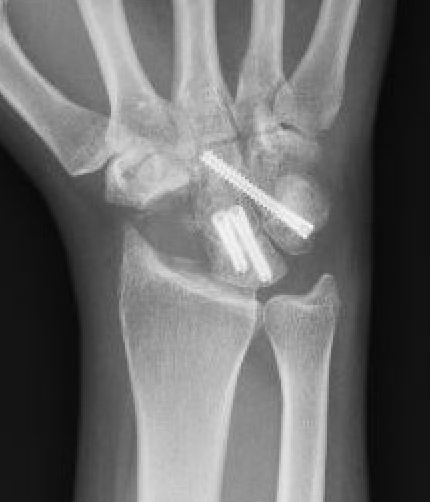

Scaphoidectomy & Limited arthrodesis

Indication

Stage II / III: Preserved radio-lunate joint

Concept scaphoidectomy + limited arthrodesis

| 4 corner fusion | 4 corner / bicolumn | 3 corner fusion | 2 corner fusion |

|---|---|---|---|

|

Capitate - lunate Triquetrum-hamate-capitate

Capitate-lunate Triquetrum-hamate |

Capitate - lunate Capitate - hamate +/- triquetrum excision |

Capitate - lunate |

Scaphoidectomy and four corner fusion

Bain et al J Hand Surg Am 2010

- 10 year follow up of scaphoidectomy and four corner fusion in 31 patients

- no change in grip strength

- flexion reduced 22%

- mean satisfaction 80%

- 2 patients underwent arthrodesis

Fixation options

K wires

Headless compression screws

Dorsal locking plates

Staples

4 corner fusion techniques

4 corner: capitate / lunate screw + triquetrum / hamate / capitate screw

Bi-column: capitate / lunate screw + triquetrum / hamate screw